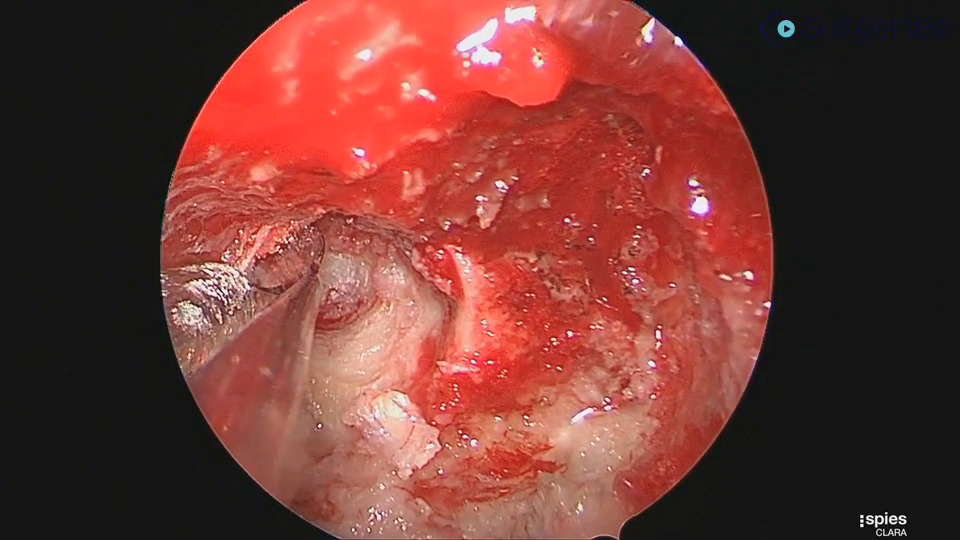

Intracapsular tonsillectomy (tonsillotomy) offers significant advantages over the extracapsular approach. By preserving residual tonsillar tissue and the capsule as a biological dressing, it protects the underlying musculature with its vessels and nerves, while delivering equivalent clinical outcomes with reduced complications of postoperative pain, dehydration, and bleeding. There is no standardized approach in performance of a tonsillotomy , unlike the extracapsular approach. Additionally, when performing a tonsillotomy on large hypertrophied tonsils, visualizing the posterior pillar—often hidden behind tonsillar tissue—can be challenging, potentially putting this muscular structure at risk for damage and negating the advantages of a tonsillotomy. We describe a standardized technique for tonsillotomy using a midline split within the tonsillar tissue, creating a “coffee bean” appearance that serves as a pivot point for retraction. This approach allows for more accurate distinction between the posterior tonsil and the pillar, resulting in more precise ablation.